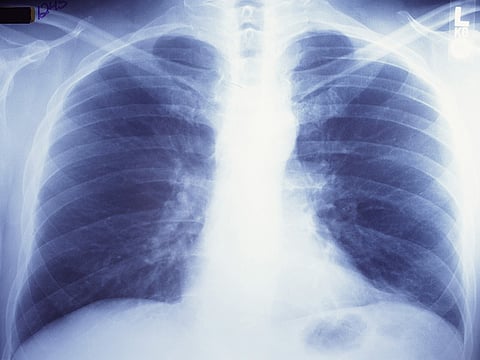

FRIDAY, Jan. 29, 2021 (HealthDay News) -- Current and former smokers are at risk for a lung disease called pulmonary fibrosis, but many aren't aware of the threat, the Pulmonary Fibrosis Foundation says.

There is no cure for the disease, which affects more than 200,000 Americans.

A recent foundation survey found that more than 80% of smokers are unfamiliar with pulmonary fibrosis. This is a concerning statistic among a group disproportionately affected by the disease.

Both smokers and nonsmokers have little awareness of the disease, and nearly 9 out of 10 Americans don't know its symptoms: shortness of breath, a dry, chronic cough and fatigue.